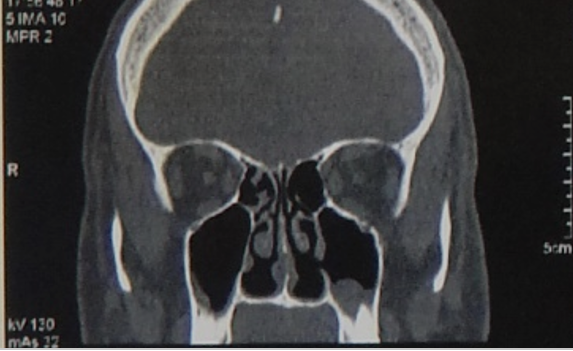

After shaped, the graft is inserted behind the pyriform aperture. Figure 3, 4, 5.

Figure 3 Close of operative view of implants placed along the lateral nasal wall just behind the piriform aperture and under the periosteum of the nasal mucosa.

Figure 4 Operative view of implants placed along the lateral nasal wall bilateral just behind the piriform aperture and under the periosteum of the nasal mucosa.